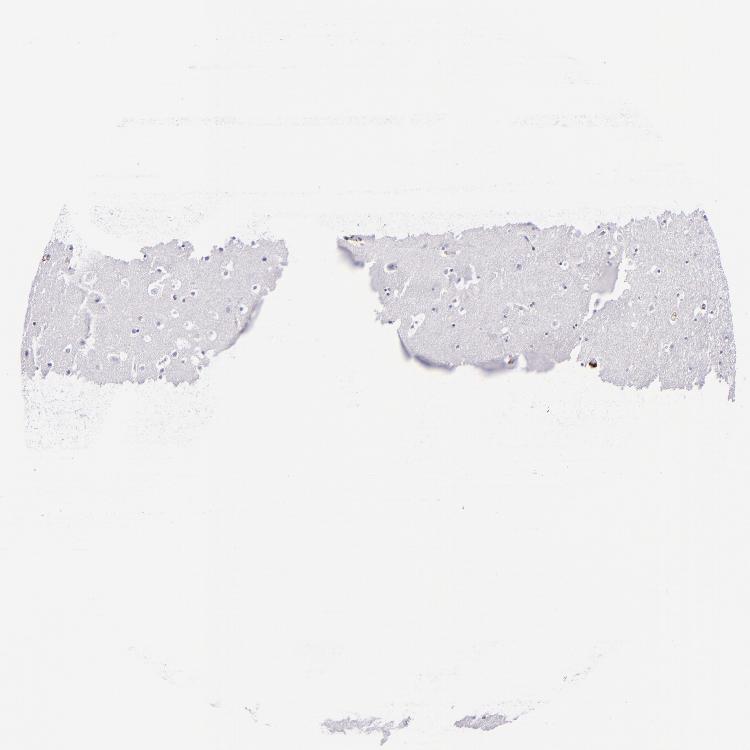

HIPPOCAMPUS - Antibody stainingi

Antibody staining in the annotated cell types in the current human tissue is reported as not detected, low, medium, or high, based on conventional immunohistochemistry profiling in selected tissues. This score is based on the combination of the staining intensity and fraction of stained cells.

Each image is clickable and will lead to virtual microscopy that enables deeper exploration of all samples and also displays staining intensity scores, fraction scores and subcellular localization as well as patient and tissue information for each sample.

Antibody HPA001804Antibody CAB002155

Glial cells Not detectedNot detected

Neuronal cells Not detectedNot detected